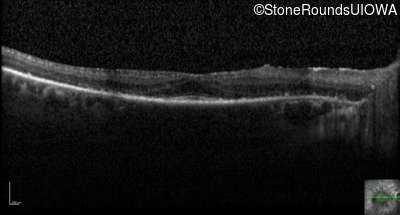

Optical Coherence Tomography - Left - 20/25 -1

Exemplar / OCT Stack